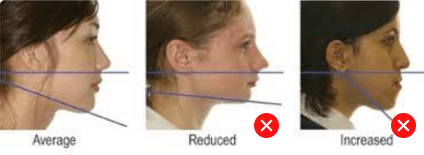

Dental Condition: Protruded side profile

(Facial Profile Analysis)

In the right hands, braces can also subtly improve overall facial harmony and aesthetics (while correcting underlying jaw and tooth alignment issues).

Not guided just by a feeling, but an artistic process guided by scientific measurements.

Unlike metal braces that often rely on extraction to create space, clear aligners allow gentle arch expansion and digitally planned movement (distalization etc) to ensure the least compromise in facial profile.

Perfect if your facial profile makes you unsuitable for extraction.